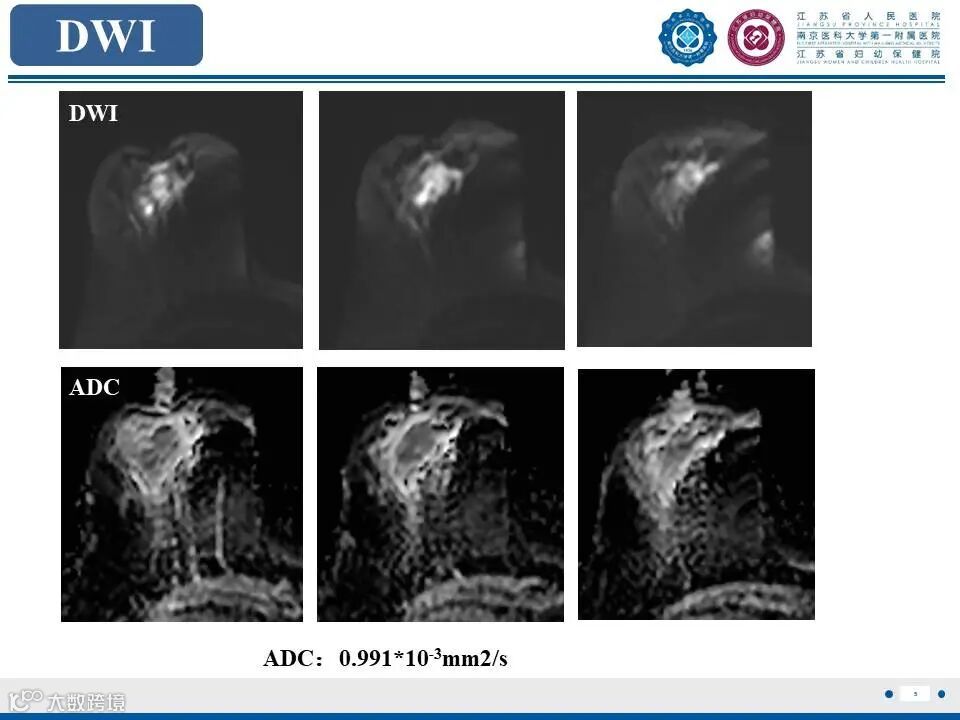

非哺乳期乳腺炎